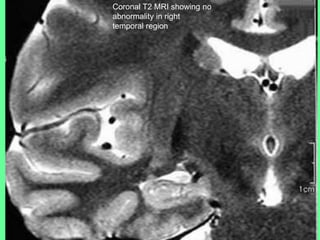

• MRI showed no anatomical abnormality (Slide 13)

Coronal T2 MRI showing no

abnormality in right

temporal region